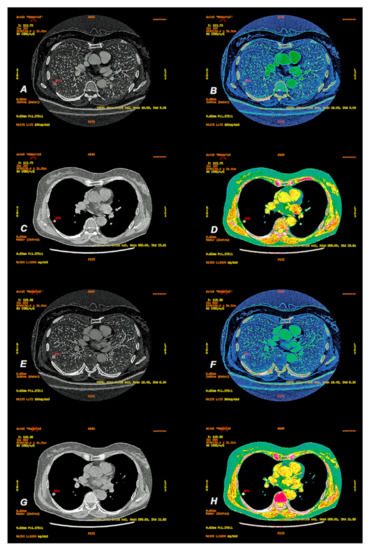

2. Materials and Methods

2.2. CT Scanning Parameters

2.3. Data Analyses

3. Results

3.1.2. Comparison of Iodine Concentration in IC Maps, Water Concentration (WC) and Radiation Absorption in Lung Tumors in AP and VP of DECT Examination